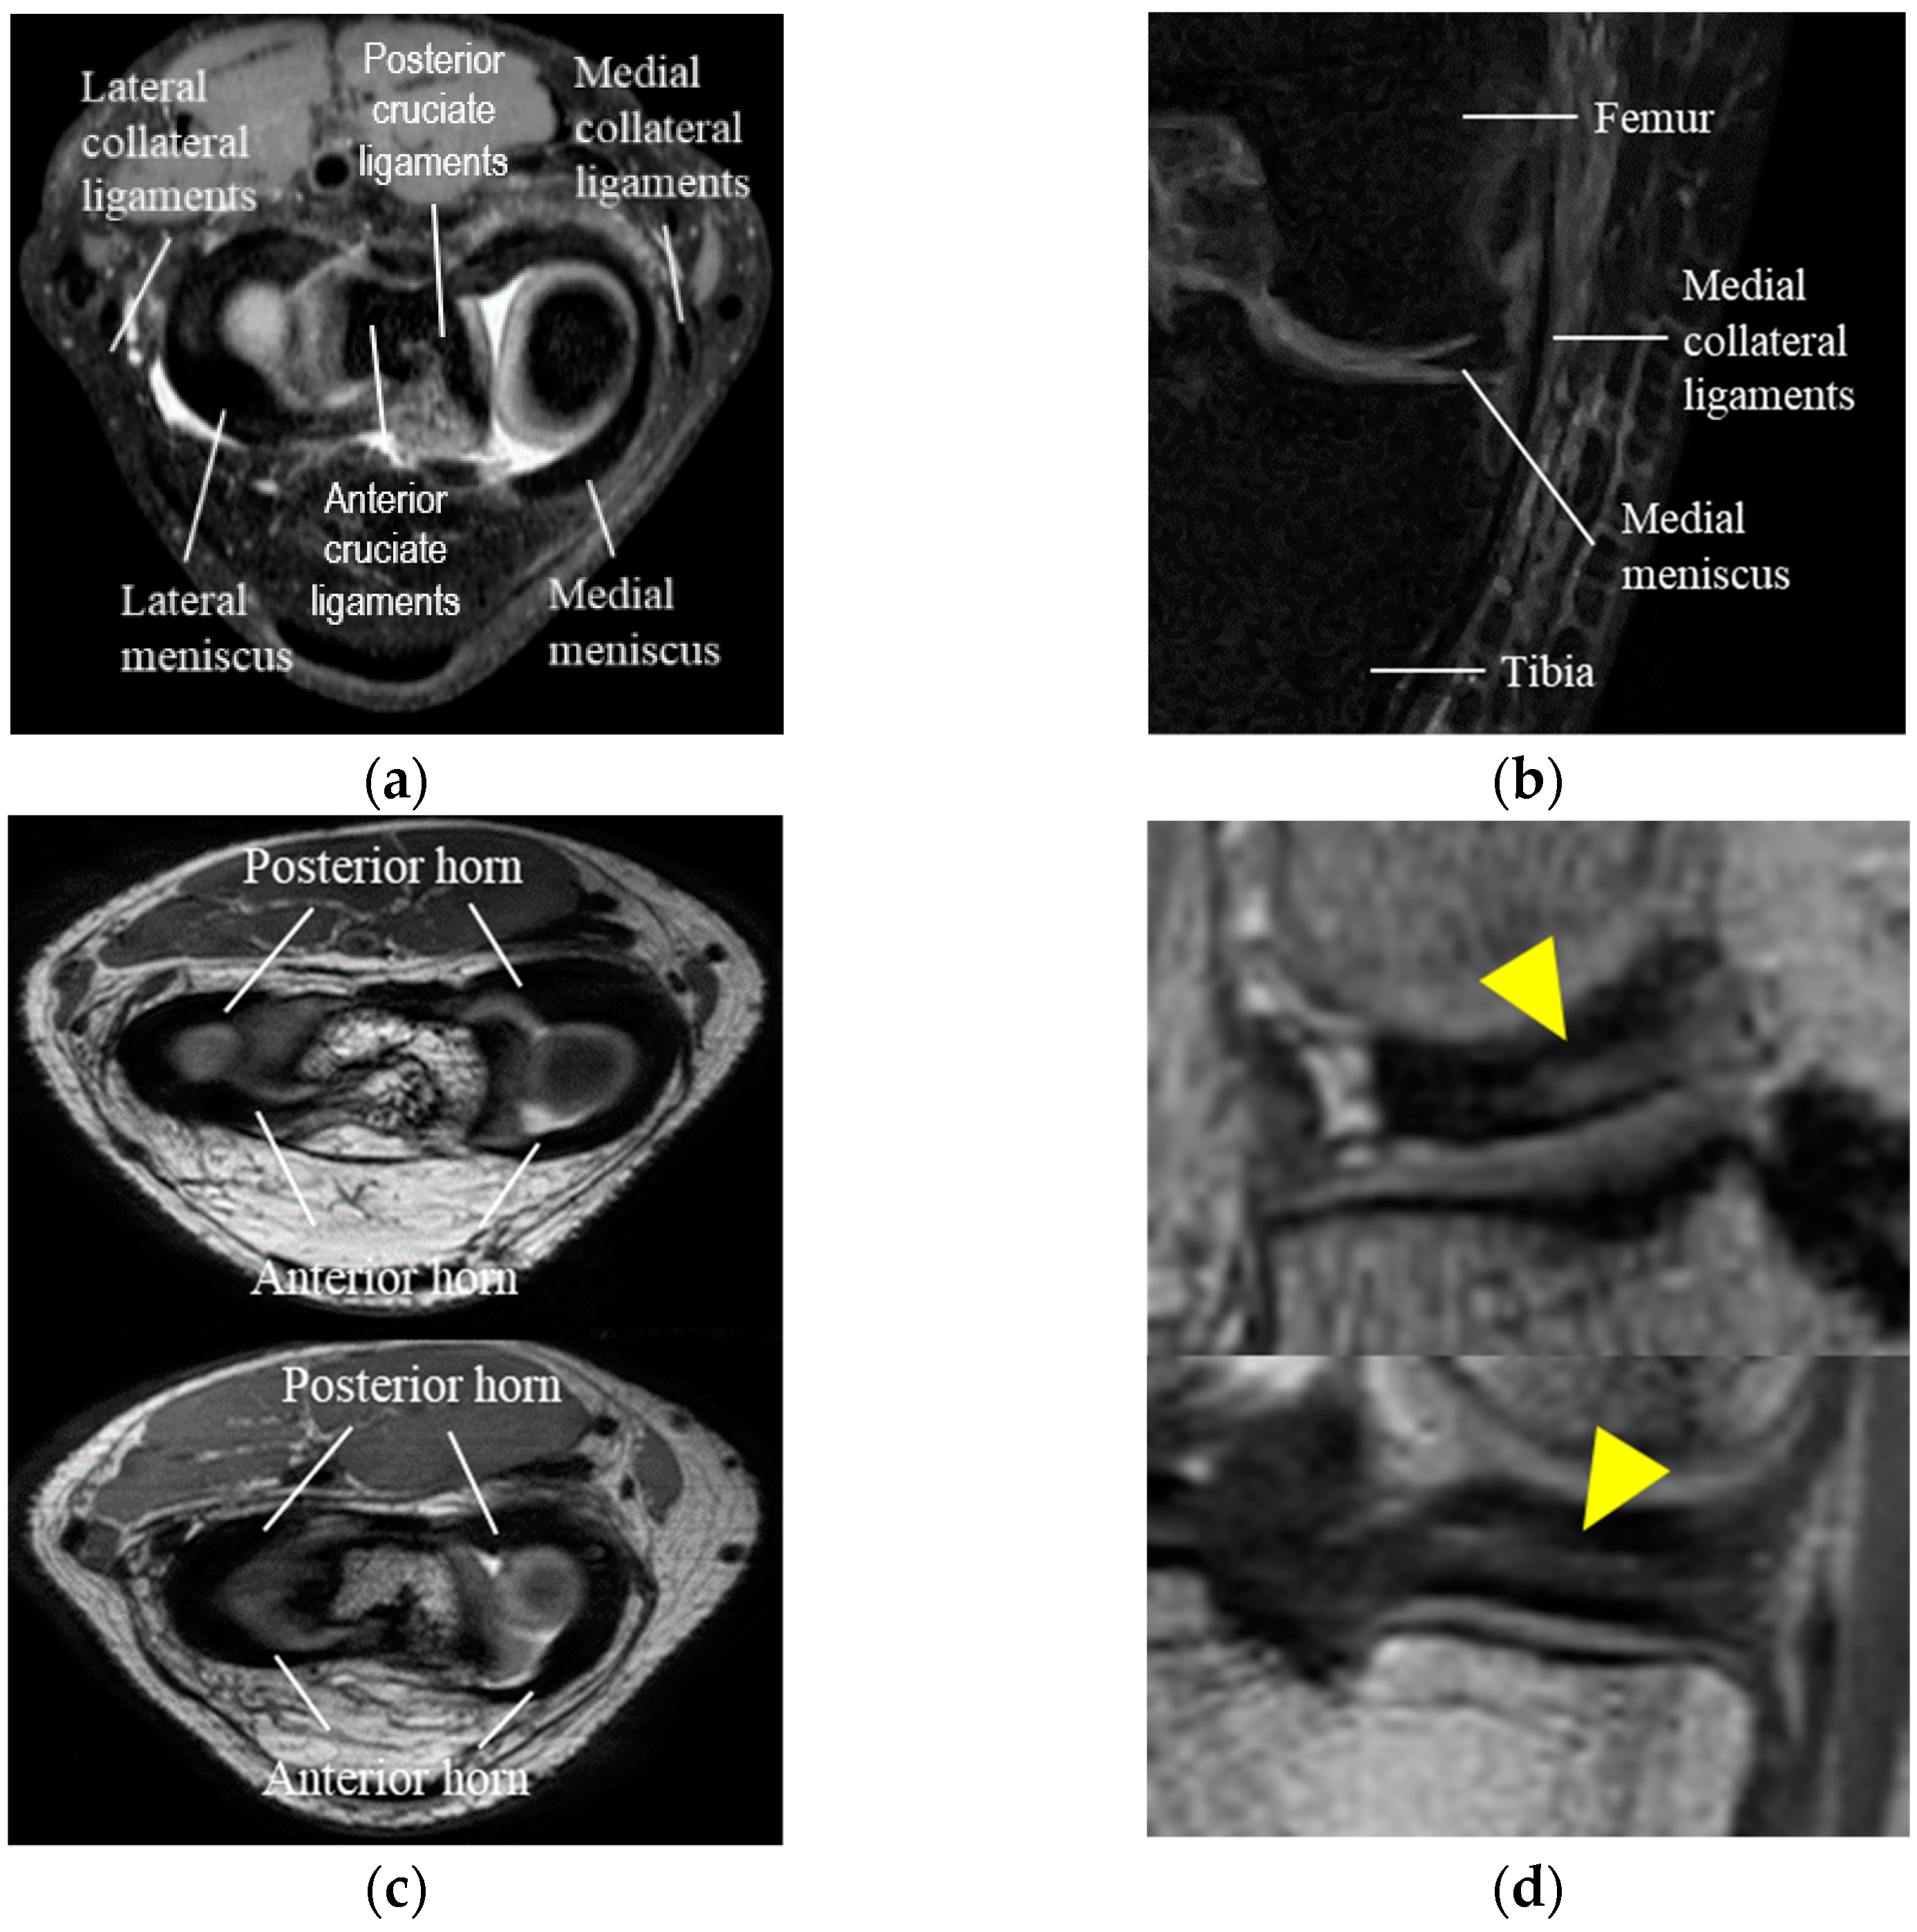

Figure 6 shows the results of a comparison between conventional adversarial learning and adversarial learning with an object-aware map. In Figure 6, the first and second columns show the results for the medial meniscus, and the third and fourth columns show the results for the lateral meniscus. As shown in Figure 6b, an outlier occurs in the posterior and anterior cruciate ligament sections and over-segmentation arises with the collateral ligament and meniscus boundary because their intensity levels are similar to that of the meniscus in the conventional adversarial network. It can be observed that outliers and over-segmentation results are prevented when using an object-aware map, as shown in Figure 6c.

Figure 6. Segmentation results of conventional adversarial network and adversarial network using an object-aware map: (a) Original image; (b) Conventional adversarial network; (c) Adversarial network using object-aware map; (d) Ground truth.